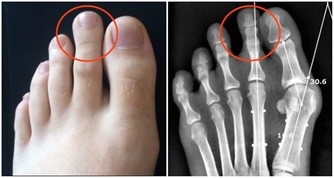

Talamantes在這次手術中失去了一個卵巢,也必須進行腹部重建手術,

讓恢復正常運作,雖然一切都還需要時間療癒,